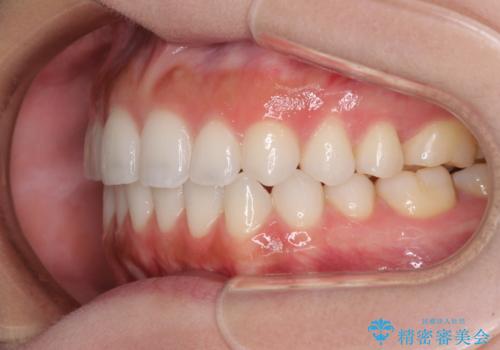

前歯のオープンバイトを治したい インビザラインでの矯正治療

- 前歯の上下スペースによる話しにくさと顎への負担を気にして来院された患者様です。

インビザラインにより上顎の大臼歯を圧下し、上下の前歯の隙間を閉じていくこととしました。

上顎の奥歯を圧下させることで、上下前歯を接触させるように計画しました。

前歯が急に接触するようになり、慣れるまで時間がかかりましたが、前歯でものが咬めるようにもなり、患者様には大変満足していただきました。